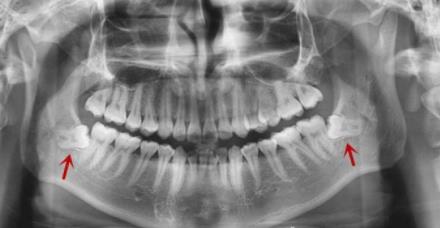

左右兩(liang) 側(ce) 兩(liang) 顆下頜智齒

如果是有2顆智齒,可以一次拔除,也可以分為(wei) 兩(liang) 次拔除。要看是屬於(yu) 同側(ce) 上下頜,還是左右兩(liang) 側(ce) ,如果是同側(ce) 上下頜智齒可以考慮一次拔除,而分布於(yu) 左右兩(liang) 側(ce) 的智齒,建議分為(wei) 兩(liang) 次拔除;